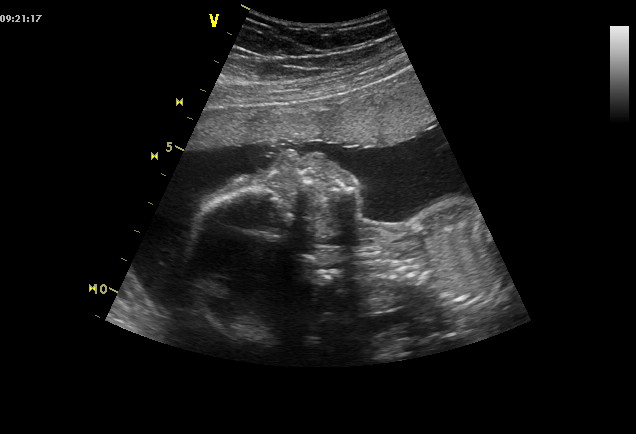

V úterý jsme šli společně na velký ultrazvuk na jednu kliniku a nevěřili jsme vlastním očím! Naše malá- velká Nikol má už skoro půl kg a je už pěkně veliká! Pan doktor kontroloval všechny Nikolčiny kosti, srdíčko, močový měchýř, ledviny, pupečník a odpovídá krásně všemu tak, jak má a prospívá. Krásně spolupracovala, takže jsme viděli opravdu všechno, protahovala se a mnula si očičko, tatínek s údivem sledoval velkou obrazovku a občas jsem ho přistihla, jak se usmívá. Každopádně to byl krásný zážitek a pan doktor pochválil krásně vznešený nosánek. Ten má po tatínkovi, je celá on z profilu.